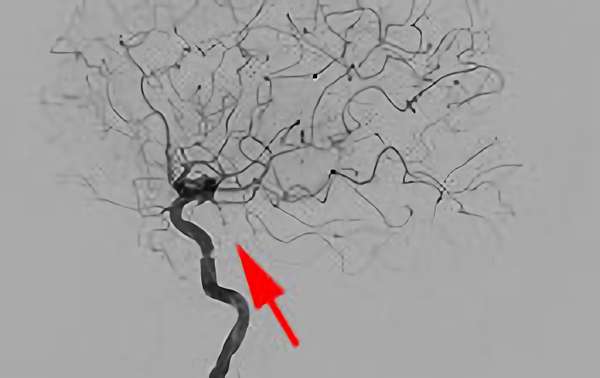

No.622 手術前

No.622 手術中

No.622 手術後